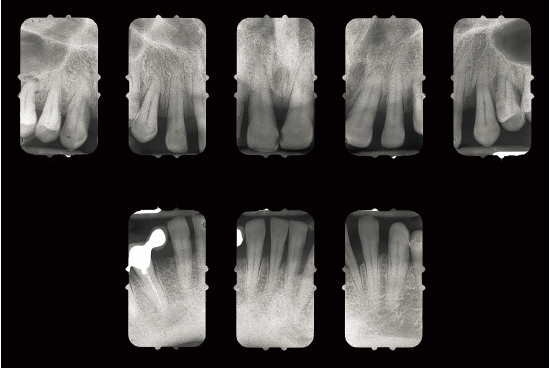

Fig 1-1a Aggressive periodontitis in a 40-year-old woman who is subject to stress and smokes one pack of cigarettes a day. The patient experienced an emotional shock 5 years earlier. A conventional treatment plan was initiated and included periodontal surgery throughout all quadrants. Professional maintenance (scaling and root planing) was carried out every 3 months, and the patient responded well.

Fig 1-1b Four years after treatment and maintenance therapy. Periodontal status has deteriorated in all areas. Observe the new attachment losses, dental migrations, and larger diastemata. It is clear that periodontal disease is not controlled. This patient’s disease was refractory to conventional treatment. Specific risk factors in this patient were underestimated.